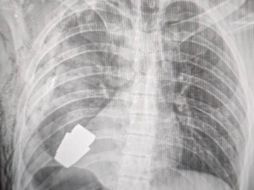

Internacional ¡Increíble! Extraen granada del pecho a un soldado ucraniano sin que explotara 12 de enero de 2023 - 16:57 hs BBC BBC News Mundo